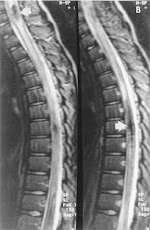

Spinal Dural Arteriovenous Fistula With Hematomyelia Caused ...

Spinal dural arteriovenous fistula with hematomyelia caused by intraparenchymal varix of draining vein Manabu Minami, MD, PhD*, Junya Hanakita, MD, PhD, Toshiyuki Takahashi, MD, PhD, ... Retrieve Here

Detection Of Spinal Dural Arteriovenous Fistulae With MR ...

Detection of Spinal Dural Arteriovenous Fistulae with MR Imaging and Contrast-Enhanced MR Angiography: Sensitivity, Specificity, and Prediction of Vertebral Level ... Return Doc